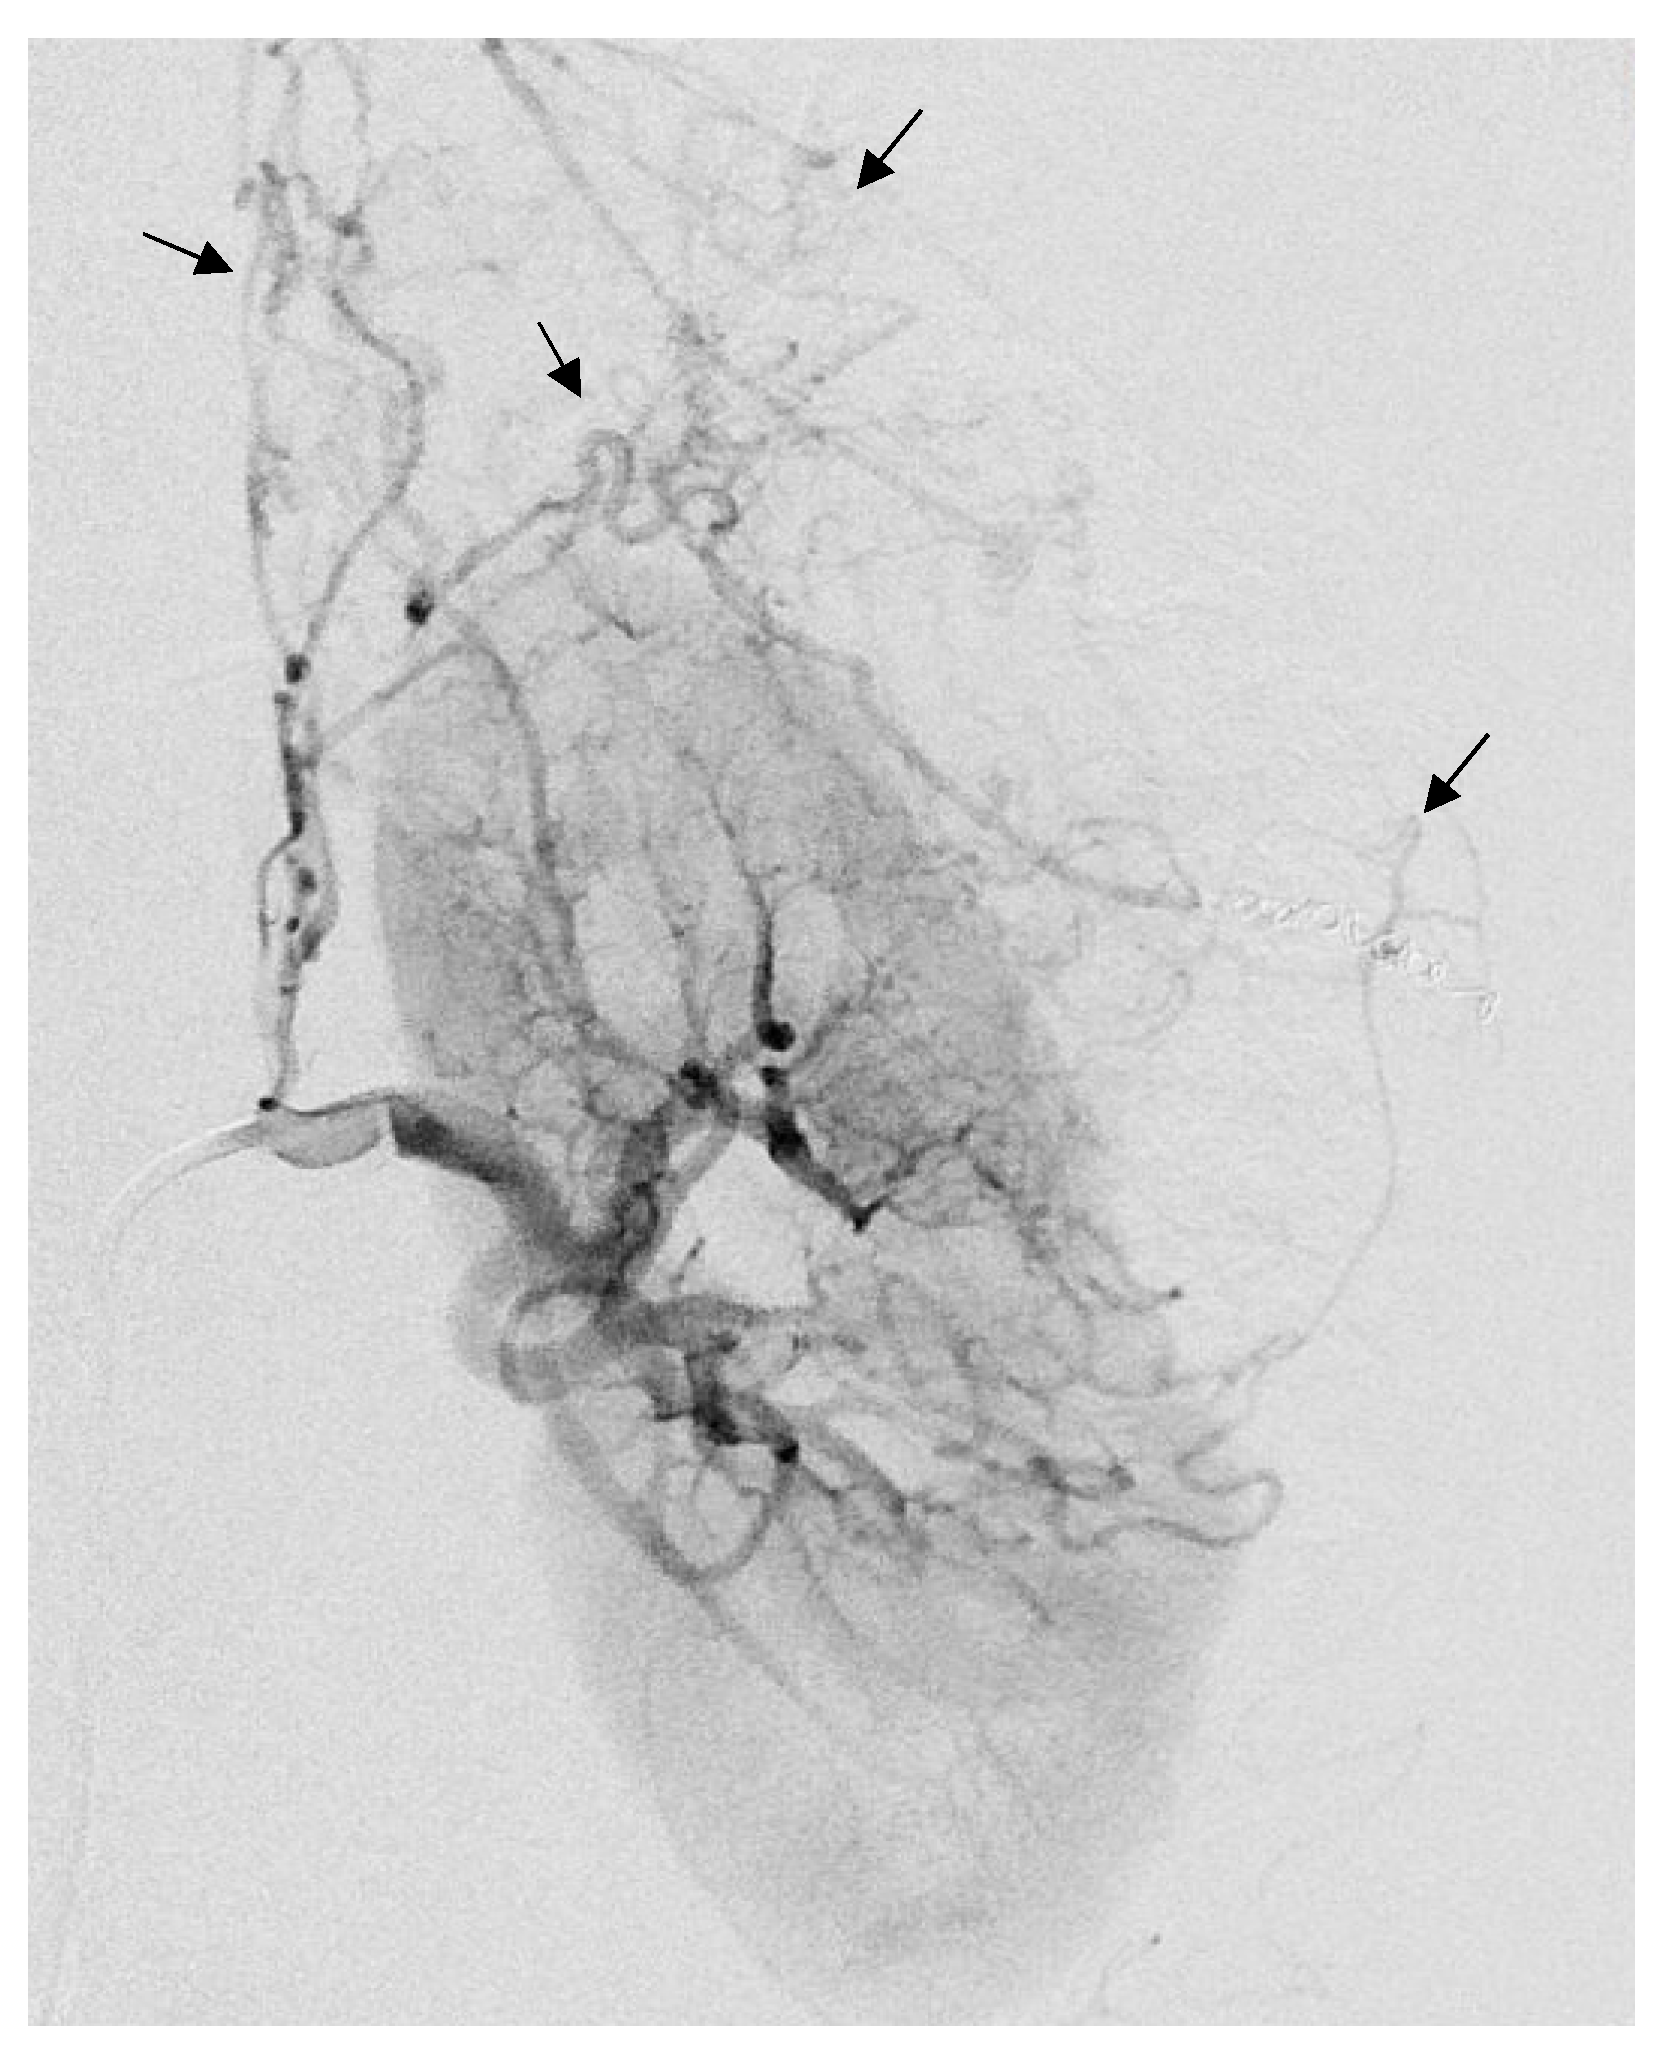

Figure 2.

Selective arterial embolization (TAE) of a large right AML. (a) Angiography shows two feeding arteries to the AML with multiples aneurysms. (b) The hypervascularity and dysplastic vessels of this AML are typical. (c) Final control after TAE of two arterial branches with ONYX 18 (6% EVOH) with technical success (lack of opacification of the AML).

Postembolization angiography performed through the 6-F catheter confirmed successful occlusion of the artery and the patency of other renal arteries branches. Technical success was defined as no opacification of the main feeding arteries and lack of AML staining on the post-TAE angiography after one embolization (primary technical success) or two (secondary technical success) (Figure 3).

The average arterial pedicle per AML was 1.4 (±0.8). Arterial pedicle count was the number of angiographically visible arterial pedicles that were a direct division of the renal artery and participated in the vascularization of the tumor. A high arterial pedicle count was significantly predictive of a second embolization (p < 0.01). The mean pre-embolization volume was 201.1 (±504.1) mm3. The majority of angiomyolipomas were exophytic (96%, n = 24). Ten patients had aneurysms on angiography (Figure 2a and Figure 3), including only five seen on pre-embolization imaging at diagnosis (Figure 1). Table 2 presents the different AML characteristics.